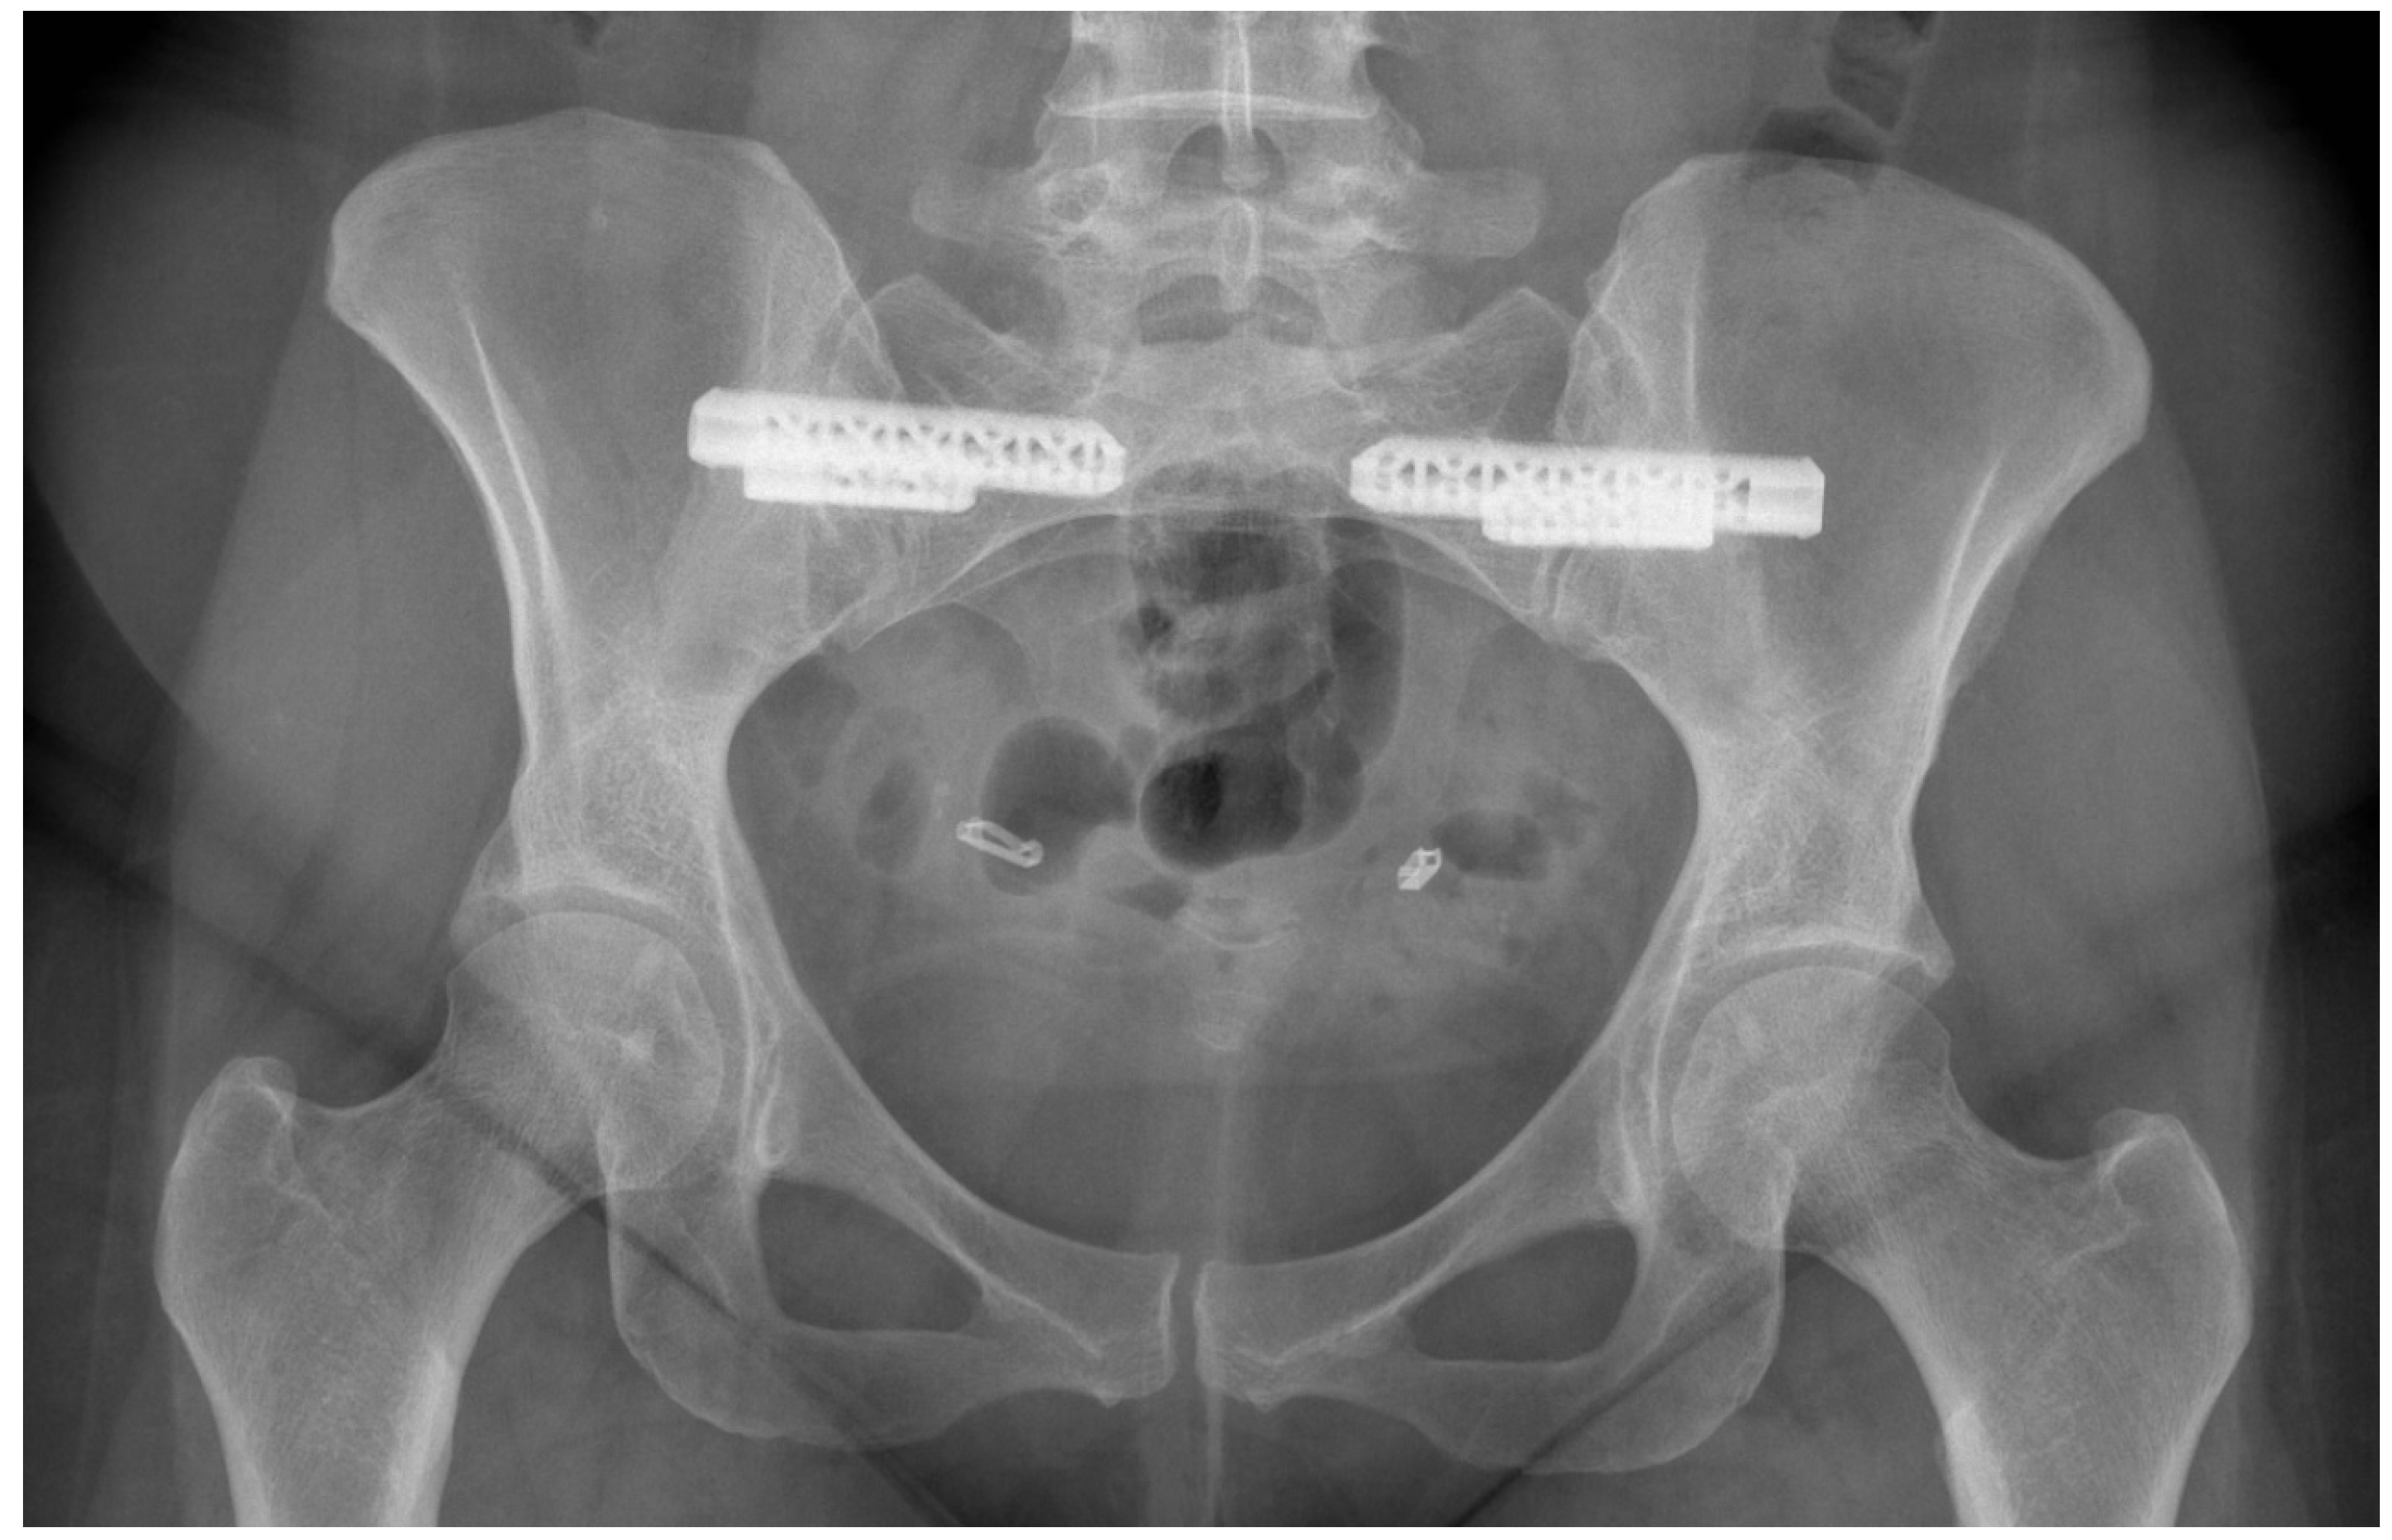

- Van Zwienen, C.M.; Van den Bosch, E.W.; Snijders, C.J.; Van Vugt, A.B. Triple pelvic ring fixation in patients with severe pregnancy-related low back and pelvic pain. Spine 2004, 29, 478–484. [Google Scholar] [CrossRef] [PubMed]

- Kibsgård, T.J.; Røise, O.; Sudmann, E.; Stuge, B. Pelvic joint fusions in patients with chronic pelvic girdle pain: A 23-year follow-up. Eur. Spine J. 2013, 22, 871–877. [Google Scholar] [CrossRef] [PubMed][Green Version]

- Dale, M.; Evans, J.; Carter, K.; O’Connell, S.; Morgan, H.; Carolan-Rees, G. iFuse Implant System for Treating Chronic Sacroiliac Joint Pain: A NICE Medical Technology Guidance. Appl. Health Econ. Health Policy 2020, 18, 363–373. [Google Scholar] [CrossRef]

- Martin, C.T.; Haase, L.; Lender, P.A.; Polly, D.W. Minimally Invasive Sacroiliac Joint Fusion: The Current Evidence. Int. J. Spine Surg. 2020, 14 (Suppl. 1), 20–29. [Google Scholar] [CrossRef] [PubMed]

- Dengler, J.; Kools, D.; Pflugmacher, R.; Gasbarrini, A.; Prestamburgo, D.; Gaetani, P.; Cher, D.; Van Eeckhoven, E.; Annertz, M.; Sturesson, B. Randomized Trial of Sacroiliac Joint Arthrodesis Compared with Conservative Management for Chronic Low Back Pain Attributed to the Sacroiliac Joint. J. Bone Joint Surg. Am. 2019, 101, 400–411. [Google Scholar] [CrossRef] [PubMed]